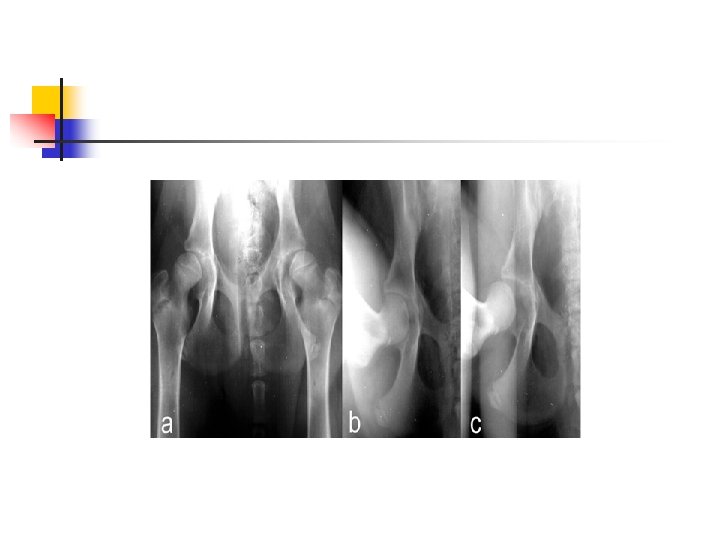

Distracted or Penn. HIP method n n Refers to a specific diagnostic technique of hip laxity information. More reliable indication of hip laxity than extended view. Stress radiographic procedure with 3 views (compression, standard extended, and distraction view). To perform this method, veterinarian or technician must be certified.

Compressed view

Distracted Positioning View